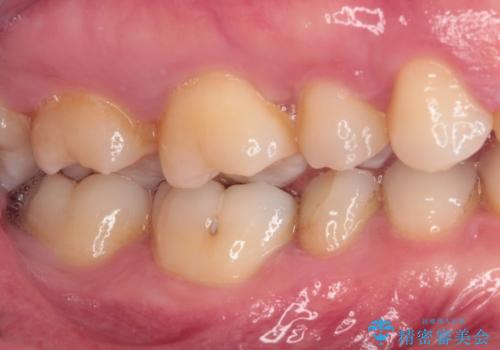

繰り返す痛み 下顎小臼歯の再根管治療

- 定期的に膿の出口ができ、食事の度に痛みを感じるとのことで来院された患者様です。

以前通われて医院にて、再度根管治療が必要であると伝えられていたようですが、レントゲン写真などの診察を行った結果、再根管治療が必要な状態でした。

根管治療を行った歯はクラウンによる補綴治療が望ましく、来院時にはクラウンが装着されていなかったため、根管治療を再度行いやすい環境でした。